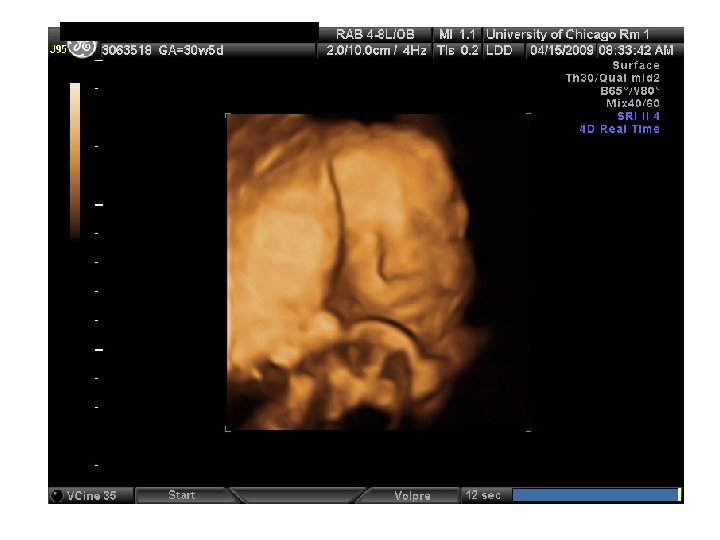

QUIZ What is Your Diagnosis? Case: Patient J. F. 30 years old, at 32 week gestation. Presented with the following pictures.

Answer: a) Trisomy 21 b) Non-immune Hydops c) Paravo virus Infection